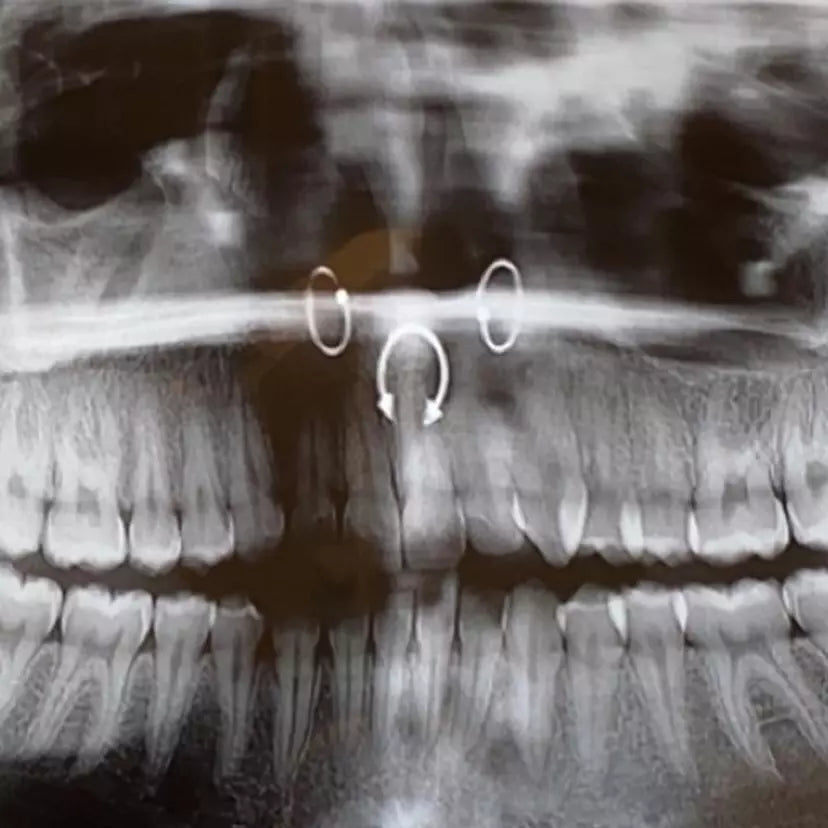

Normal jewelry can obstruct areas the surgeon needs to access. Even if they don’t, the surgeon may accidentally loosen an end while doing what they have to. (This would be the absolute WORST possible time for the end to come off of your tongue ring. Swallowing it might be the least awful outcome because choking on it is a possibility.) Another potential crisis is if the medical team needs to defibrillate you or use some other electrical device like an electrocautery tool. The electricity combined with metal jewelry can lead to some nasty burns. You’re already dealing with enough without that kind of injury on top of everything. And, while not especially likely, there remains the possibility of needing an MRI. While quality jewelry should not interact with the machine due to not being magnetic, one never knows for sure and if your jewelry does turn out to have some kind of magnetic component, it will turn into shrapnel in the MRI machine. Ouch.

Retainers can be used in most piercings. They are available in flat back labret styles, nose rings, septum rings, and even nipple and navel rings. The most common materials are PTFE, which is the flexible plastic seen in pregnancy belly rings, and glass. Glass is strongly recommended over PTFE because it is entirely inert and can be worn for long periods of time while there are allegations that PTFE may leach chemicals into the human body. However, you aren’t going to have it in for very long, so the choice is yours. If you think you may ever need to use it again in your lifetime, glass is probably the way to go because it can be sanitized more easily and is more durable if cared for properly.